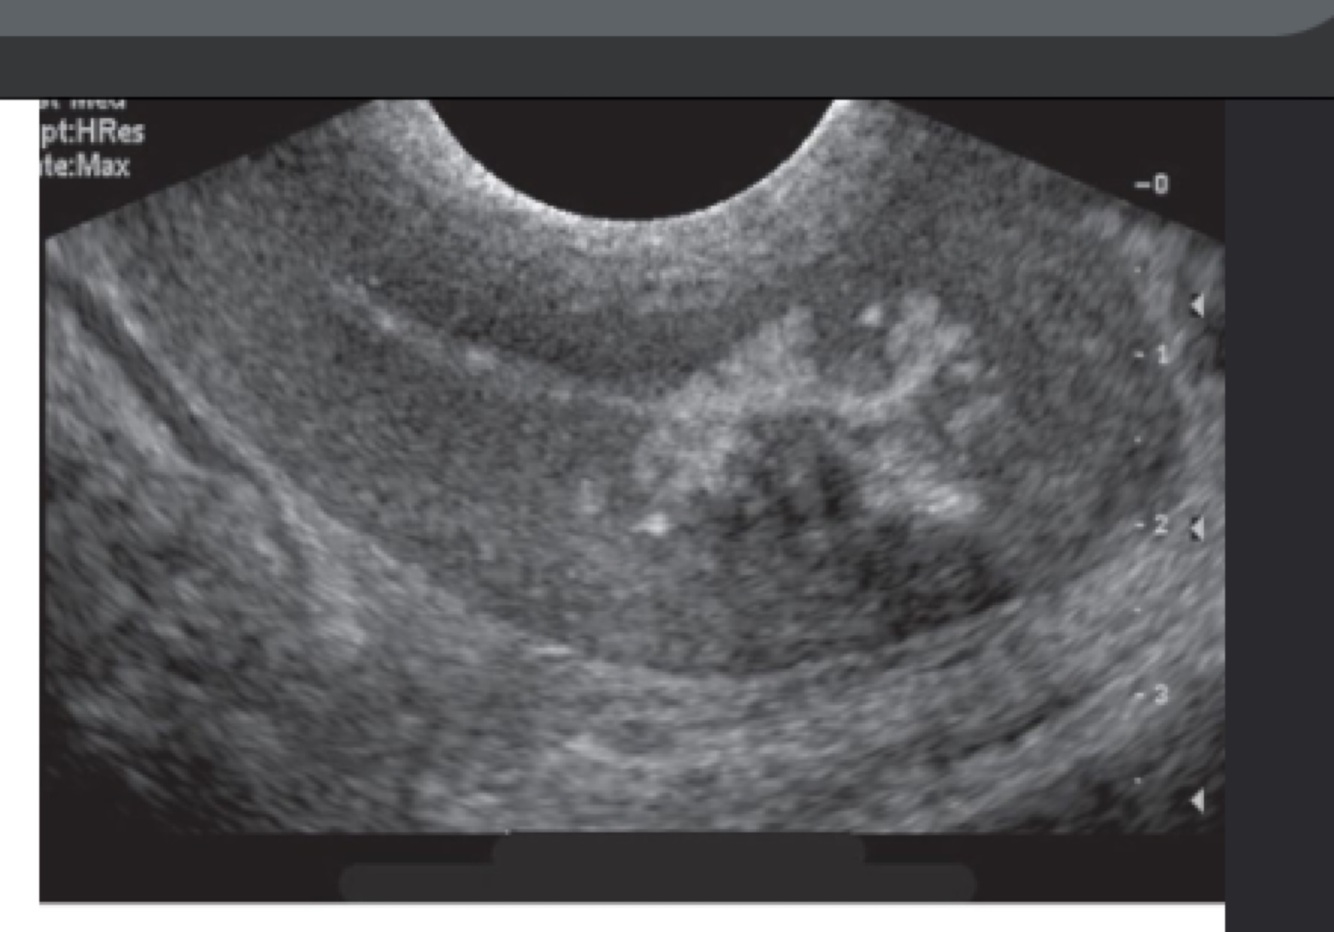

What does this image demonstrate?

A

Morbidly adherent placenta

What is morbidly adherent placenta (MAP)?

Abnormal placental implantation into uterine wall

What is the ultrasound features of MAPs? 5

1. Loss of hypoechoic plane in the myometrium beneath the placenta bed 2. Presence of multiple placenta lacunae 3. Loss of hyperechoic line separating the urinary bladder from the uterus 4. Thinning of the myometrium to less than 1mm 5. Buldging of placenta into organs adjacent to the uterus, causing a mass like lesion protruding out from the uterine wall